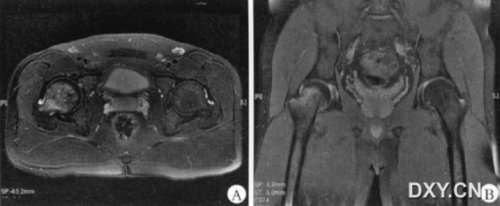

图1为同一病人。图1a:左侧股骨头颈T1WI呈低信号,信号不均匀,边界不清。图1b:病灶T2WI上为略高信号。图1c:病灶STIR为高信号,关节腔少量积液。图1d:3个月后复查,病灶STIR高信号消失,关节腔少量积液已吸收。